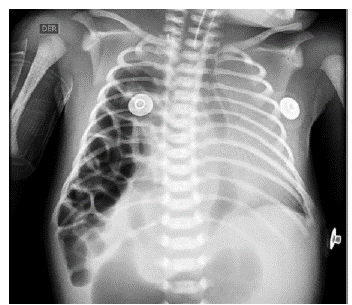

El paciente continuó en cuidados intensivos hasta su estabilización, que se alcanza a los dos días de vida, con un Índice de Oxigenación 11.2, fracción inspirada de oxígeno (FiO2) 0.45, saturación de oxígeno 98% y gasto urinario de 5 cc/kg/hora; lo que permitió el abordaje quirúrgico, el cual se realiza por laparotomía subcostal derecha, hallando lo siguiente: hernia diafragmática posterolateral derecha tipo C (Ver figura 2A), asas intestinales delgadas y colon en hemitórax derecho, hígado en hipocondrio izquierdo de ubicación medial a la posición anatómica habitual, adherencias fibrosas fuertes entre región subhepática y asas delgadas (Bandas de Ladd) y malrotación intestinal (Ver figura 2B).

Fuente: autores.

Figura 2 A. Defecto diafragmático parcialmente corregido con sutura. B. Bandas de Ladd.

En el posquirúrgico inmediato el paciente se traslada a cuidado intensivo, manteniendo soporte ventilatorio y hemodinámico, observando hallazgos radiológicos torácicos (Ver figura 3) de neumotórax en más del 90% del campo pulmonar derecho con colapso parcial del pulmón en este hemitórax, esto debido a la hipoplasia pulmonar, más no a un neumotórax verdadero. Adicionalmente, con hallazgos ecocardiográficos de hipertensión pulmonar severa, desviación a la izquierda del tabique interventricular e hipertrofia ventricular derecha y sin otro tipo de hallazgo patológico morfofuncional cardiaco, por lo que se adiciona manejo con óxido nítrico inhalado, obteniendo adecuada respuesta inicial.

Figura 3 Radiografía de tórax en el postquirúrgico inmediato.